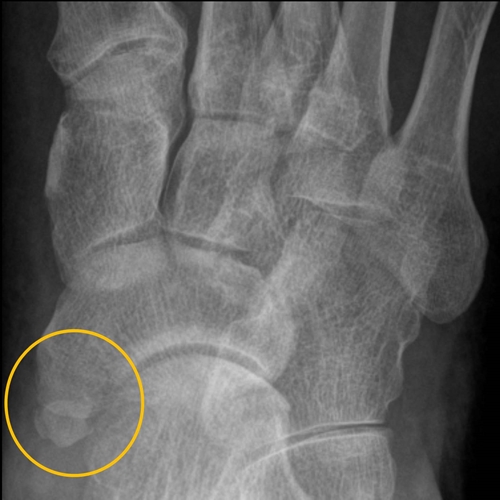

사진에서 살펴본 것과 같이 주상골(navicular bone)은 단일한 뼈(bone)입니다. 하지만 부주상골증후군(accessory navicular syndrome)은 주상골(navicular bone)이 하나가 아닌 증상과도 같습니다. 그래서 그 이외의 뼈(bone)를 부주상골(accessory navicular bone)이라 부릅니다. 기본적으로 부주상골(accessory navicular bone)은 더 작은 크기(small size)로 형성되어있으며, 그 위치는 부주상골(accessory navicular bone)이라는 이름답게 주상골(navicular bone) 옆(lateral)에 자리 잡게 됩니다.

부주상골(accessory navicular bone)은 주상골(navicular bone)과 융합되지 않아 발생되는 증후군(syndrome)입니다. (융합되지 않는 이유도 나열한다면 정말 많겠지만 그걸 떠나서라도) 하지만 부주상골(accessory navicular bone)의 크기(size)나 무게(weight)가 크지 않다면, 부주상골증후군(accessory navicular syndrome)이 있다고 해서 신체가 강하게 느낄 정도로 발과 발목에서의 통증(foot & ankle pain)을 유발하지는 않습니다. 부주상골(accessory navicular bone)이 크면 클수록, 그리고 그 위치(position)가 더 아플 수 있을 만한 장소에 위치하면 위치할수록 통증(pain)도 더욱 증가됩니다.

부주상골증후군(accessory navicular syndrome)을 겪고 있는 대상자의 발과 발목(foot & ankle)을 보고 있자면, 당연히 부주상골(accessory navicular bone)이 자리 잡은 위치적인 특성으로 인해, 발목뼈(tarsal bone)들의 전체 면적(area)이 증가하게 됩니다. 여기에 부주상골(accessory navicular bone)의 위치(position)나 크기(size)가 주상골(navicular bone)로부터 더욱 도드라질 수 있는 상태에 놓여있다면 더욱 그러할 것입니다. 이런 사람들은 소위 발볼이 넓어진 만큼, 평발(flat foot)처럼 관찰되기 쉽습니다. (추가적으로 더 언급하지 않겠지만, 선천적 평발(innate flat foot)의 경우 이것을 보상(compensation)하기 위한 목적으로 부주상골(accessory navicular bone)이 형성될 가능성도 높습니다.) 특히나 정상 경우보다 아치가 더 낮은 평발(flat foot)을 가지고 있다면, 대상자의 발(foot)은 부주상골(accessory navicular bone)로 인해 더욱 심화된 평발(flat foot)처럼 관찰될 것입니다. 이것은 발 전체 사이즈(foot size)를 계속해서 증가시키는 요인이 되며, 신발(shoes)을 착용함에 있어 발의 내측 아치(medial arch of foot) 부분과 부주상골(accessory navicular bone)이 자리 잡은 영역이 신발 내부 구조(internal structure of shoes)와 너무 가깝게, 그러니까 더 좁은 공간(narrow space)을 허용하게 될 것입니다. 이것은 알다시피 발과 발목(foot & ankle)에 있어서 가동성과 안정성 결함(mobility & stability defect)을 크게 부추길 수 있는 신발(shoes) 착용에서 오는 결함(defect)입니다. 이전에 발과 신발(foot & shoes)에 대해서 작성한 글이 있기 때문에, 이것이 얼마나 인체에 유해한 스트레스가 될 수 있는지에 대해 생각해볼 수 있습니다.